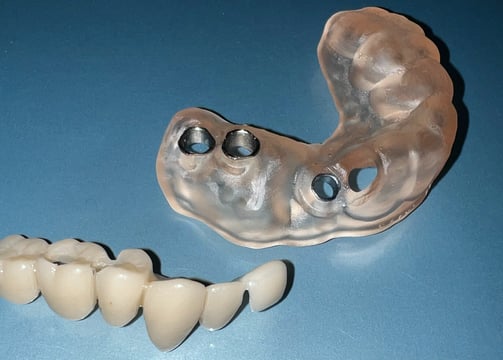

Modulo planificación, diseño, impresión y montaje de guías quirúrgicas (adquiere todos los conocimientos para poder prepararte tus propios casos)

Modulo planificación, diseño, impresión y montaje de guías quirúrgicas